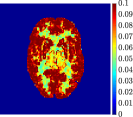

Figure 4, Figure 5, and Figure 6 show the mean images computed over the ten reconstructions obtained by the methods reg-AS-TR, reg-GN, and by the Matlab routine lsqcurvefit implementing a standard Trust-Region-Reflective least-squares algorithm [11, 10]. We used the noise-free IF and the perturbed IF with and of noise, respectively. Figure 7 contains mean and standard deviation values of the kinetic parameters computed over the ten reconstructions and over each one of the four homogeneous regions, for each one of the three noise levels on the IF.

In general, reg-AS-TR and lsqcurvefit seem to provide similar mean reconstructions, although uncertainties associated to lsqcurvefit are significantly bigger. On the other hand reg-GN seems to systematically underestimate the parameter values within region . Furthermore and as expected, for all methods the quality of the parametric reconstructions deteriorates with increasing noise levels; this is more clear from the and parametric images, probably due to the different sensitivities of the data with respect to the model parameters [37]. In reg-GN and lsqcurvefit some artifacts can be observed at the edges of the homogeneous regions, especially around region and region , whereas the effect of regularization in reg-AS-TR results in a reduced presence of artifacts while the structure of the regions is preserved. This general trend is confirmed by the error-bar plots of Figure 7. Finally, the frames in Figure 8 corresponding to reg-AS-TR show a significant improvement of the image quality with respect to what is provided by the other two approaches.